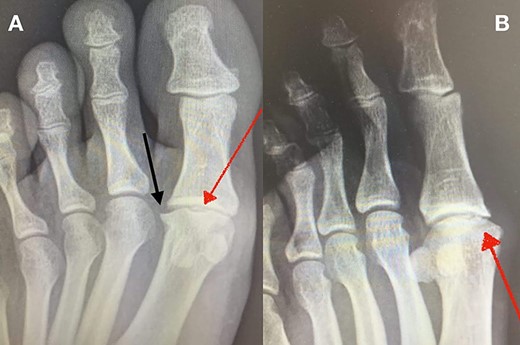

(A + B): (A) Anteroposterior, weight-bearing, X-ray view of the left foot. The red arrow shows a lytic lesion of the subchondral bone, indicating a possible OD lesion on the MH. The black arrow shows the formation of a small, lateral osteophyte. (B) Oblique X-ray view of the left foot. The red arrow shows again radiolucency of the cortical bone as well as small fragmentation of the MH.

Standing anteroposterior (AP), oblique and lateral radiographs of the affected foot were taken. On the AP and oblique views, an OD lesion of the 1st MH was visible (lytic lesion of the subchondral bone and subchondral sclerosis formation) with a lateral-forming osteophyte (Fig. 1A and B). Magnetic resonance imaging (MRI) of the left foot clearly shows the osteochondral defect of the 1st MH (Figs 2 and 3).